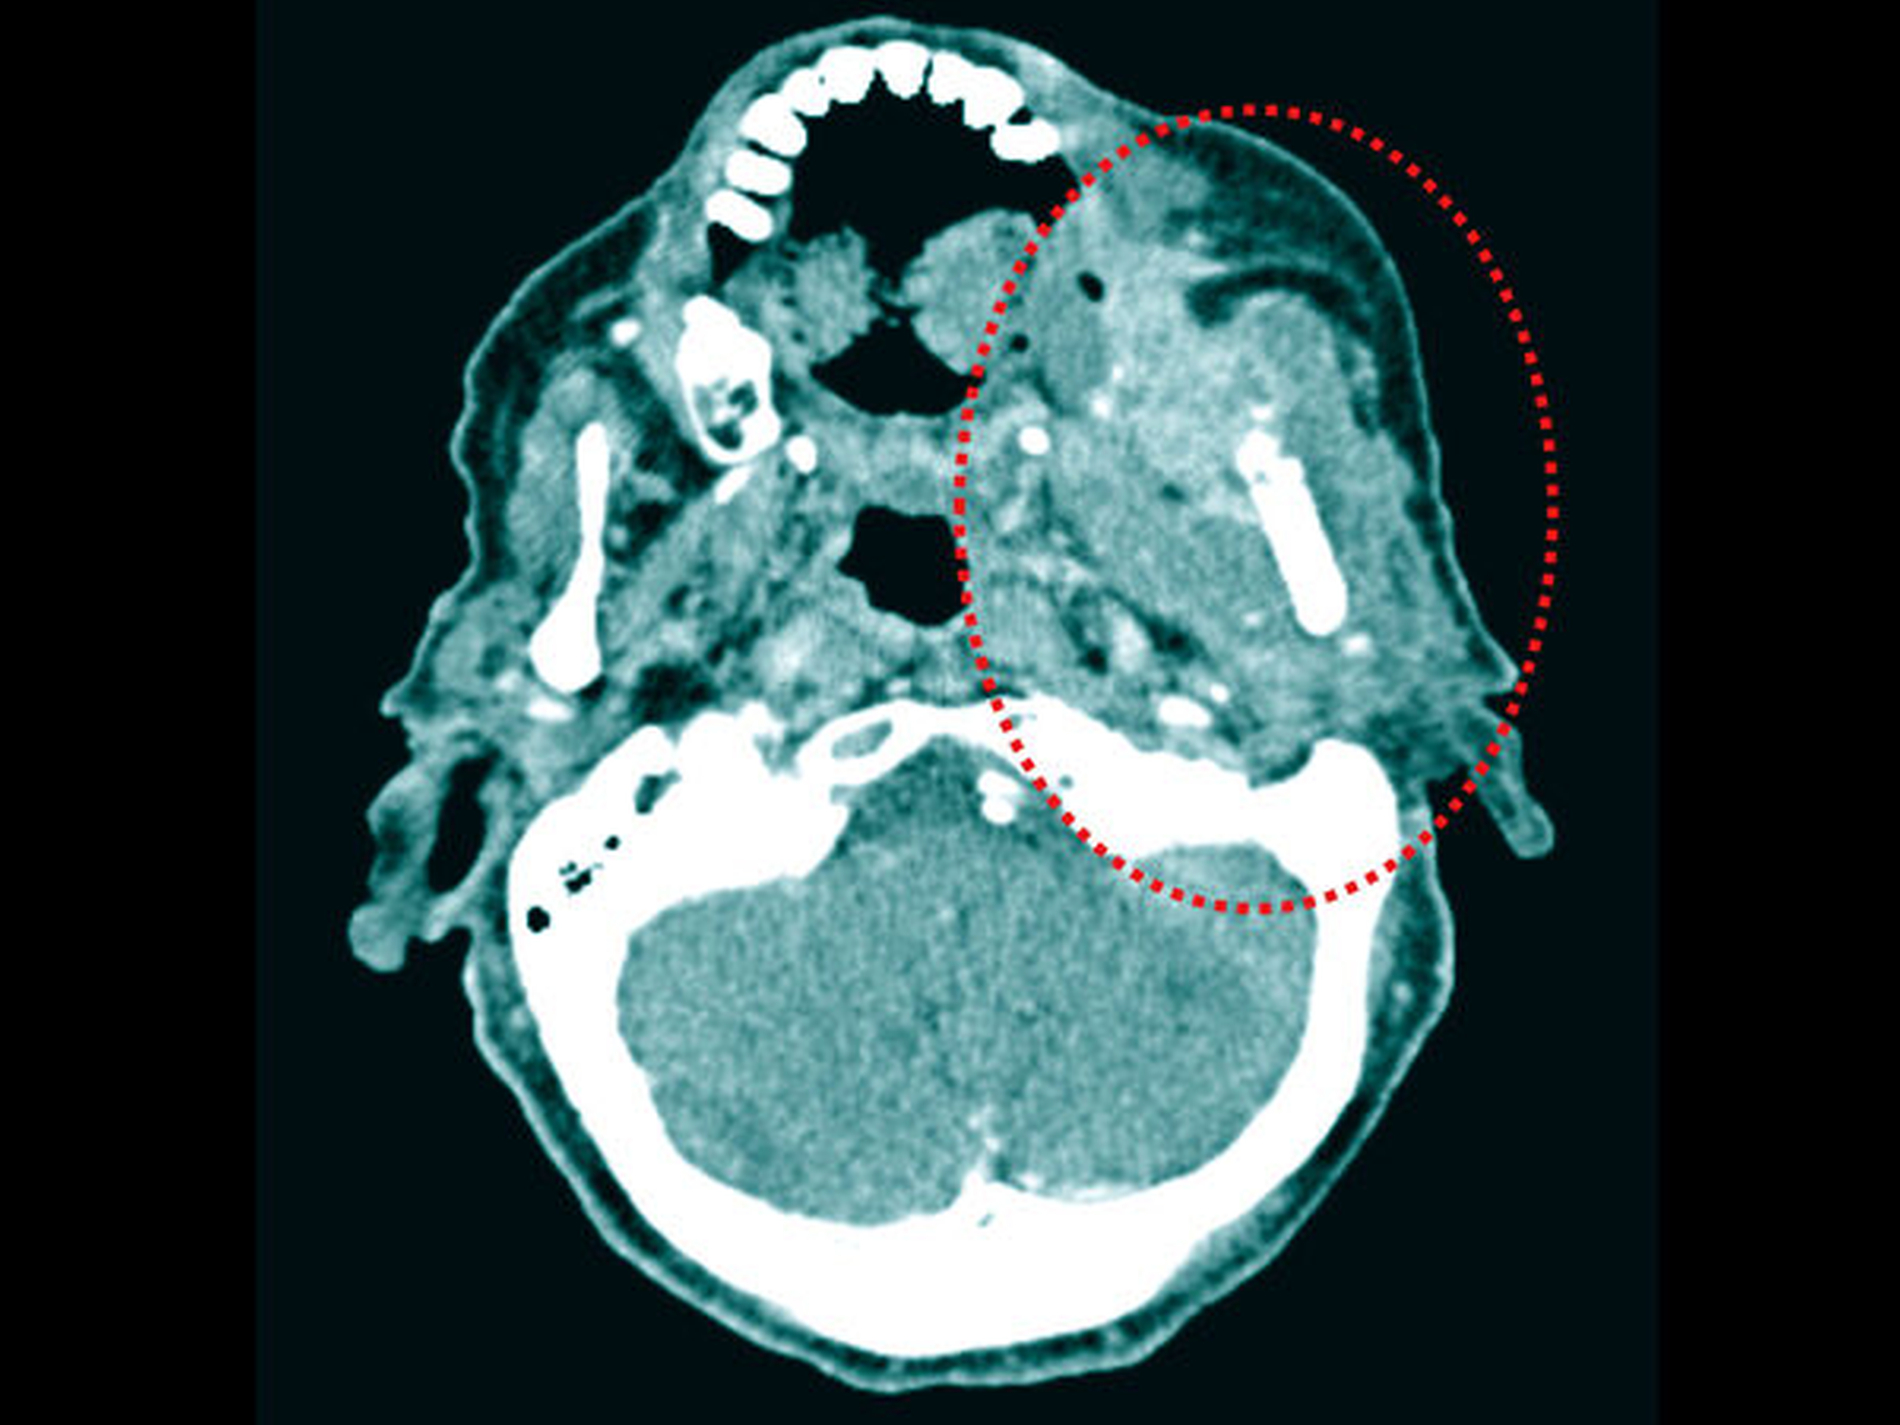

Klinisch wurde zunächst die Verdachtsdiagnose einer ausgedehnten Osteo-radionekrose beziehungsweise einer ossären Spätmetastase des vorbekannten Mammakarzinoms gestellt. Die CT-Bildgebung bestätigte eine ausgedehnte Osteolyse von regio 37 bis hin zur Schädelbasis mit allseitigem Befall der knöchernen Kortikalis (Abbildung 2). Zusätzlich zeigte sich eine massive, den linken aufsteigenden Unterkiefer- ast vollständig umschließende Raumforderung (Abbildung 3).